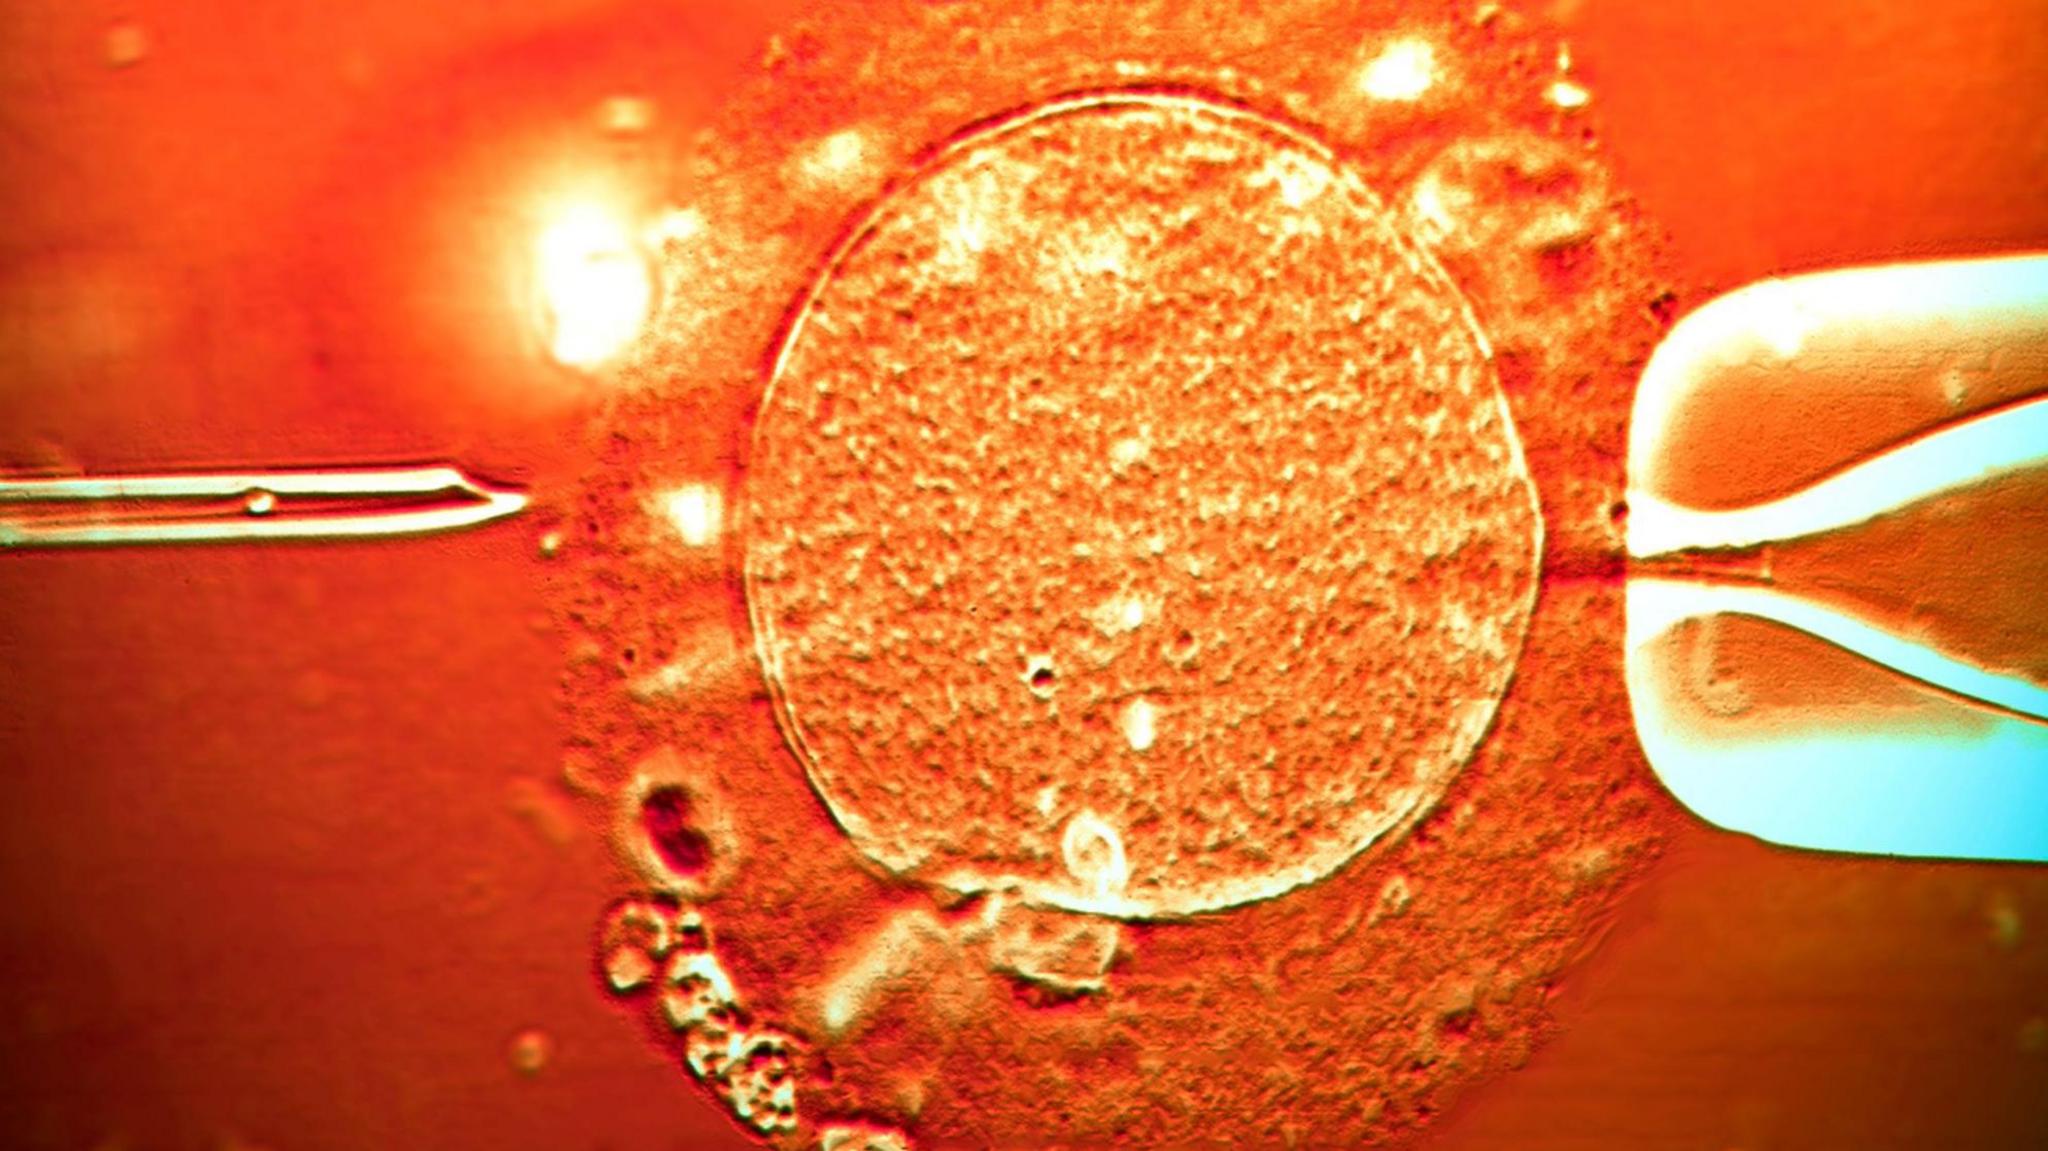

Color light micrograph of a micro-needle (left) about to inject human sperm into a human egg cell (centre) being held in place by a pipette (right). IVF treatment.

A sperm donor who unknowingly harboured a genetic mutation that dramatically raises the risk of cancer has fathered at least 197 children across Europe,  Read More